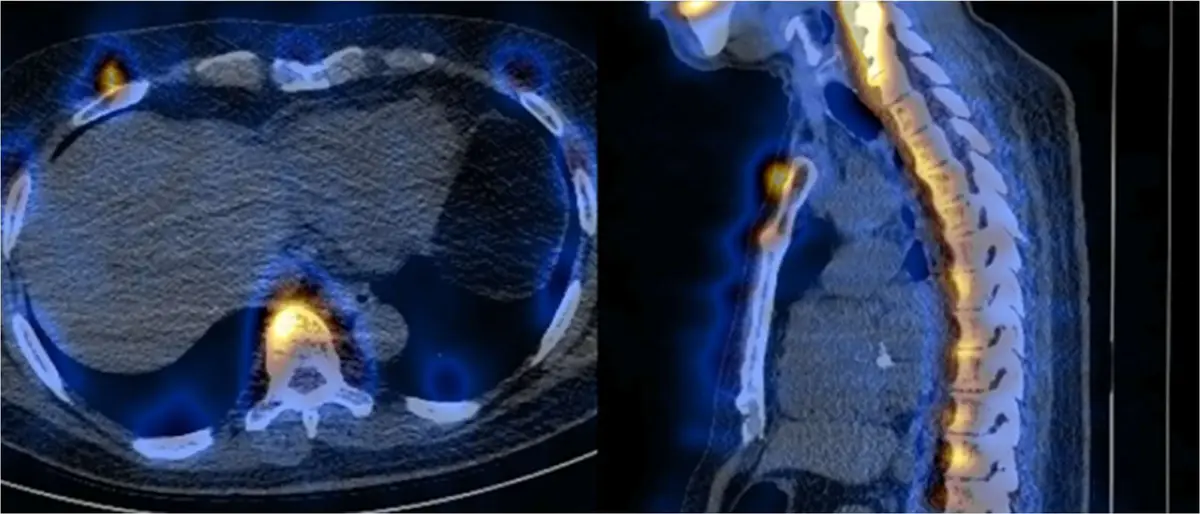

以 SPECT/CT 進行骨骼斷層掃描,融合的影像如圖所示,其假影最可能的成因為何?

- 左圖 (橫斷面 Axial view):影像顯示極高強度的放射性藥物攝取(呈現明亮的黃 / 橘色區塊,為典型骨骼掃描的表現)落在脊椎骨前方的軟組織,以及胸壁兩側肋骨的外側。對照背景的 CT 灰階解剖影像,實際的骨骼結構(脊椎本體、肋骨)反而沒有對應的高攝取訊號。

- 右圖 (矢狀面 Sagittal view):可以明顯觀察到整條脊柱的高放射性攝取區,均勻地向人體腹側(anterior)偏移,落在脊椎前方空間;胸骨的攝取訊號也同樣向前偏移,甚至超出了體表輪廓。

- 綜合判讀:正常的骨骼造影中,放射性同位素(如 99mTc-MDP)應高度積聚於骨骼的羥磷灰石 (hydroxyapatite) 晶體結構內。然而,此融合影像 (Fused image) 顯示放射性藥物攝取區整體偏離了 CT 影像上的真實骨骼解剖位置,產生了明顯的空間平移,此為經典的影像錯位 (misregistration) 現象。

本題測驗醫事放射師對 SPECT/CT 複合影像系統假影的辨識與成因理解。透過仔細觀察題目提供的正中矢狀面及橫斷面融合影像,可輕易發現影像中明亮的示蹤劑分布位置與實際解剖骨骼位置發生了整體的平移錯開。這種純粹的功能性與解剖性影像在空間上的不吻合,就是典型的 misregistration (對位不良)。